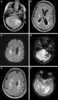

CADASIL or CADASIL syndrome, involving cerebral autosomal dominant arteriopathy with subcortical infarcts and leukoencephalopathy, is the most common form of hereditary stroke disorder, and is thought to be caused by mutations of the Notch 3 gene on chromosome 19. The disease belongs to a family of disorders called the leukodystrophies. [Source: Wikipedia ]